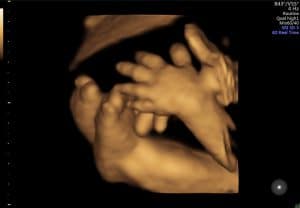

Nadat de baby met een 2D echo in beeld is gebracht en de ligging duidelijk is, wordt er met een 3D echo extra kleur aan de doorsnede toegevoegd. Je ziet dan drie dimensies (3D), namelijk lengte, breedte en diepte. Waar je met een 2D echo als het ware door je kindje heen kijkt, kijk je er met een 3D echo omheen. Dus alles wat bijvoorbeeld voor het gezichtje van de baby ligt is met een 3D echo wel te zien. Door de 3D beelden te combineren met 4D echografie, krijg je bewegende 3D beelden. Dit maakt het een ‘live’ ervaring om naar je kindje te kijken.

De foto’s die je vaak op internet ziet en ook op deze site zijn optimale beelden. Dan bedoelen we een zeer gunstige ligging van de baby, slanke zwangere en mogelijk niet de eerste zwangerschap, waardoor de wand van de baarmoeder soepeler is. Zie deze foto’s dus niet als vergelijking voor je eigen 3/4D-echo.